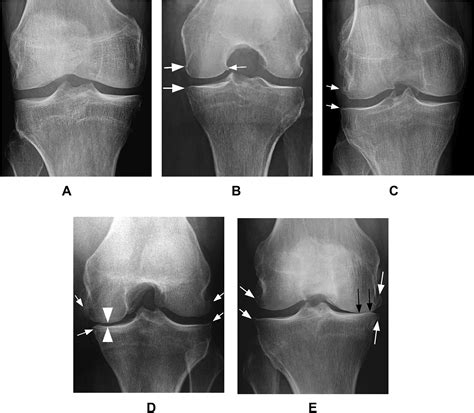

The Kellgren Lawrence Scale is the most widely utilized system for classifying the severity of knee osteoarthritis (OA) based on radiographic findings. Originally developed in 1957, this grading system analyzes X-ray images to look for specific signs of joint wear and tear, such as joint space narrowing, the formation of bone spurs (osteophytes), and structural deformities.

By assigning a grade from 0 to 4, medical professionals can communicate the extent of damage consistently. This standardization is vital for clinical research and patient care because it allows for a clear, objective measurement of how much a joint has deteriorated over time.

Breaking Down the Grades

The scale functions on a five-point system, where 0 represents a healthy joint and 4 represents severe, advanced disease. Below is a breakdown of how each grade is interpreted:

Grade Classification Description

Grade 0 None No radiographic features of osteoarthritis are present.

Grade 1 Doubtful Minute osteophytes of doubtful clinical significance.

Grade 2 Mild Definite osteophytes and possible joint space narrowing.

Grade 3 Moderate Multiple osteophytes, definite joint space narrowing, and some sclerosis.

Grade 4 Severe Large osteophytes, marked joint space narrowing, severe sclerosis, and bony deformity.